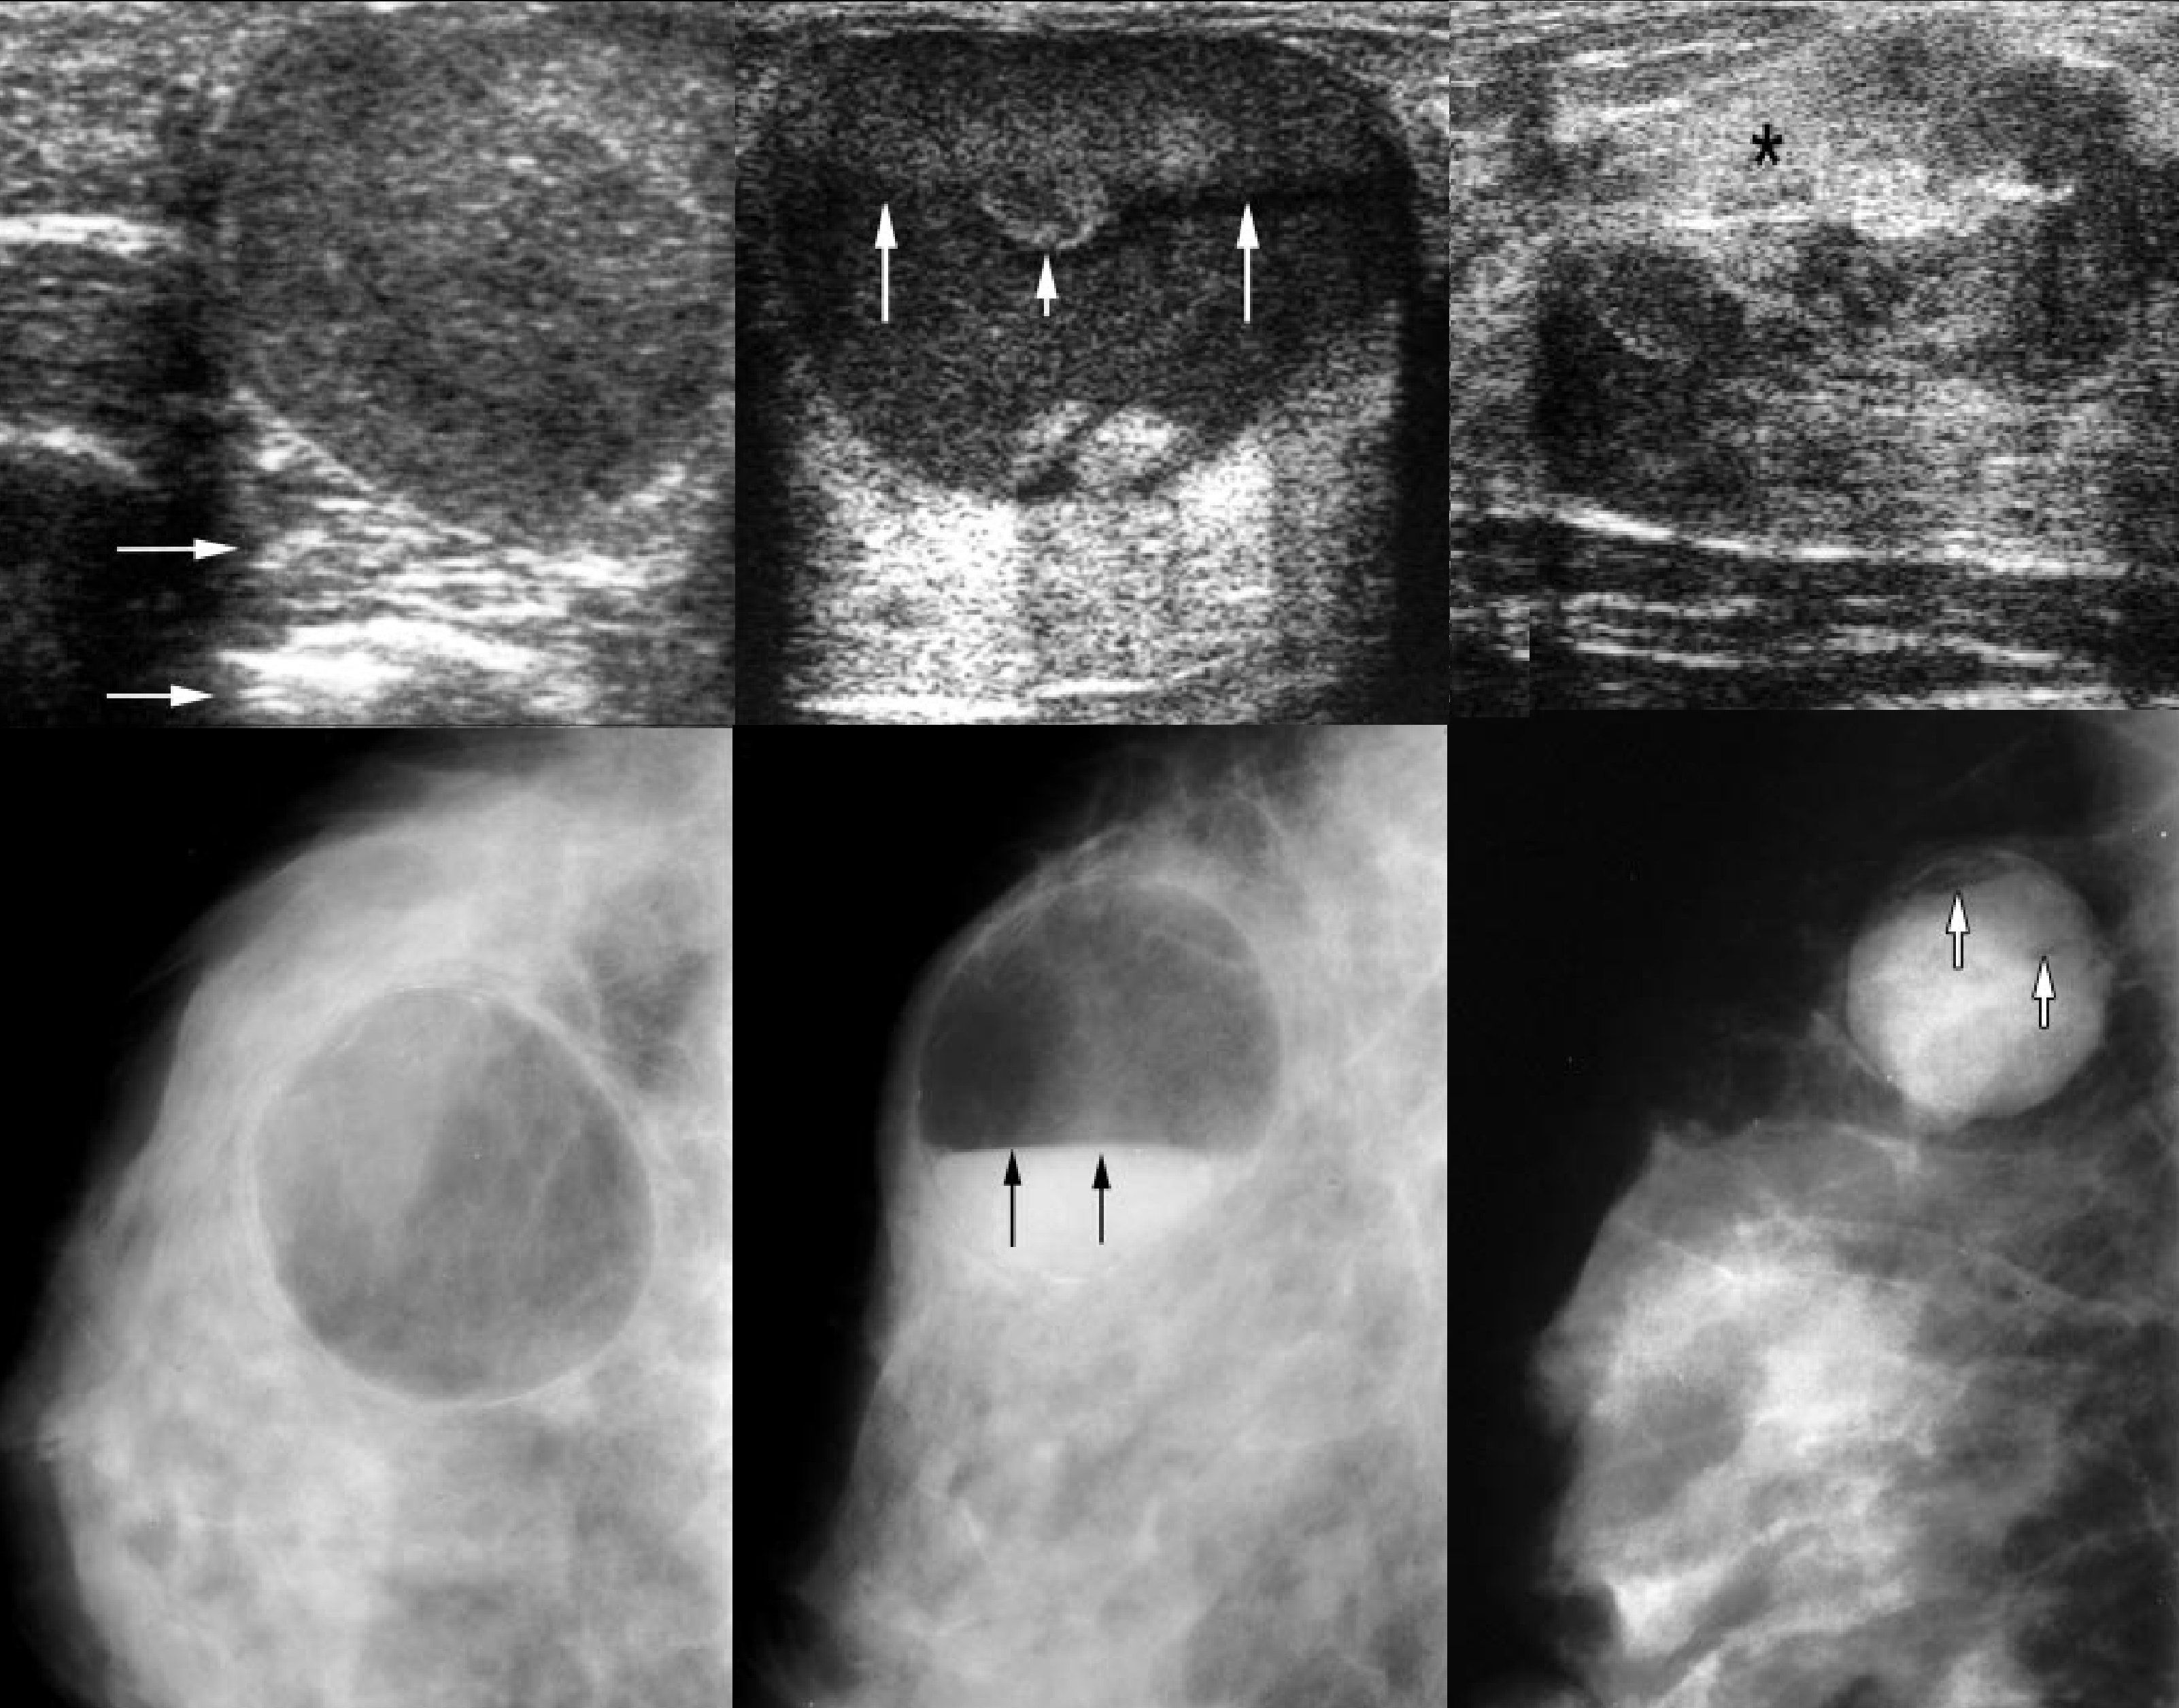

Фиброзно-кистозная мастопатия на УЗИ

Киста на снимке маммографии